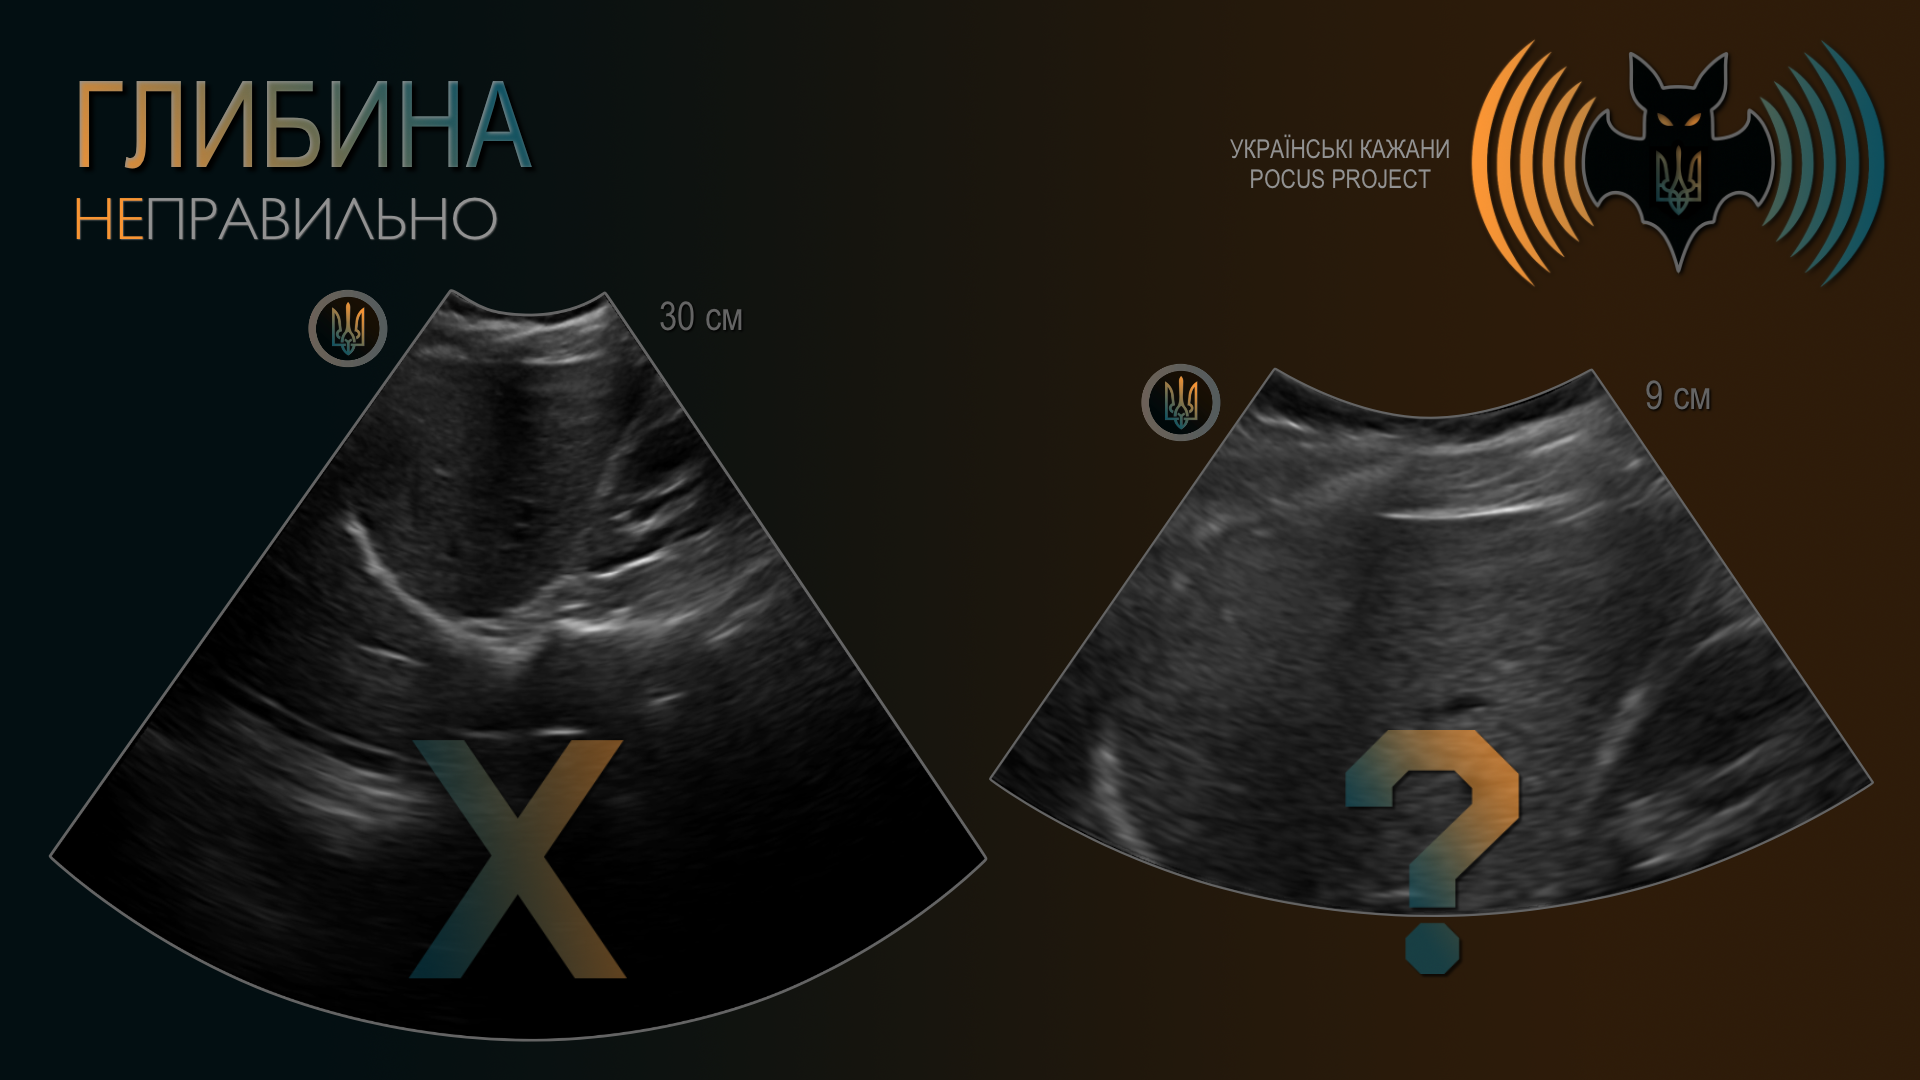

ГЛИБИНА (DEPTH): Поняття глибини є досить очевидним. Якісне зображення не повинно мати більшу частину екрана, зайняту структурами без клінічного значення. Водночас поганою звичкою є встановлення глибини таким чином, що за досліджуваною структурою не залишається жодного вільного простору. Найкраще починати з надмірної глибини та поступово зменшувати її, а не навпаки — з надто малої глибини з ризиком пропустити важливі знахідки. Загалом рекомендовано, щоб приблизно третина або чверть екрана залишалася за межами ділянки, яку ви оцінюєте.